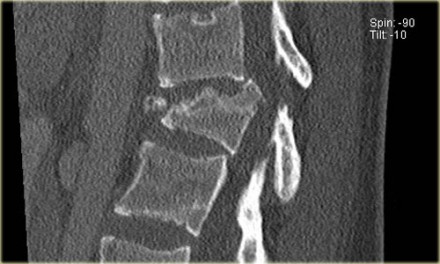

Patients with a rigid spine are more at risk for translation or distraction.

Here is a patient with distraction on the anterior side.

Notice the rigid spine and how easily this major injury can be overlooked.

This patient had a motorcycle accident.

The MRI demonstrates rupture of the flava ligaments, interspinous and supraspinous ligaments as well as fracture of the posterior elements and compression of the vertebral body.

A posterior spondylodesis was performed.